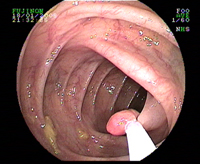

Biopsie exerese à la pince d'un polype